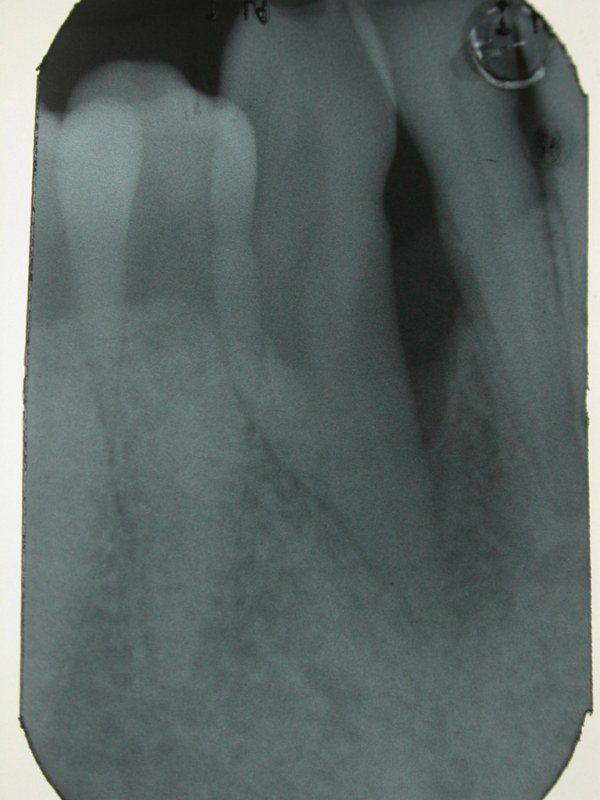

2° Caso: retrazioni gengivali